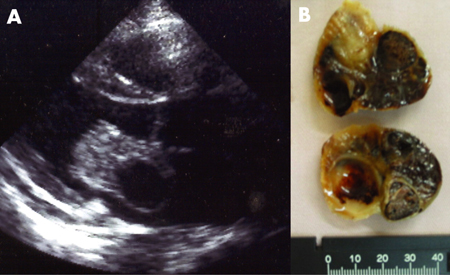

[Figure caption and citation for the preceding image starts]: Mixoma atrial identificado em ecocardiografia (A) e após ressecção cirúrgica (B)Extraído de: HH Ho, WK Seto, E Wang, WH Chow. BMJ Case Reports 2009; doi:10.1136/bcr.2006.093781 [Citation ends].